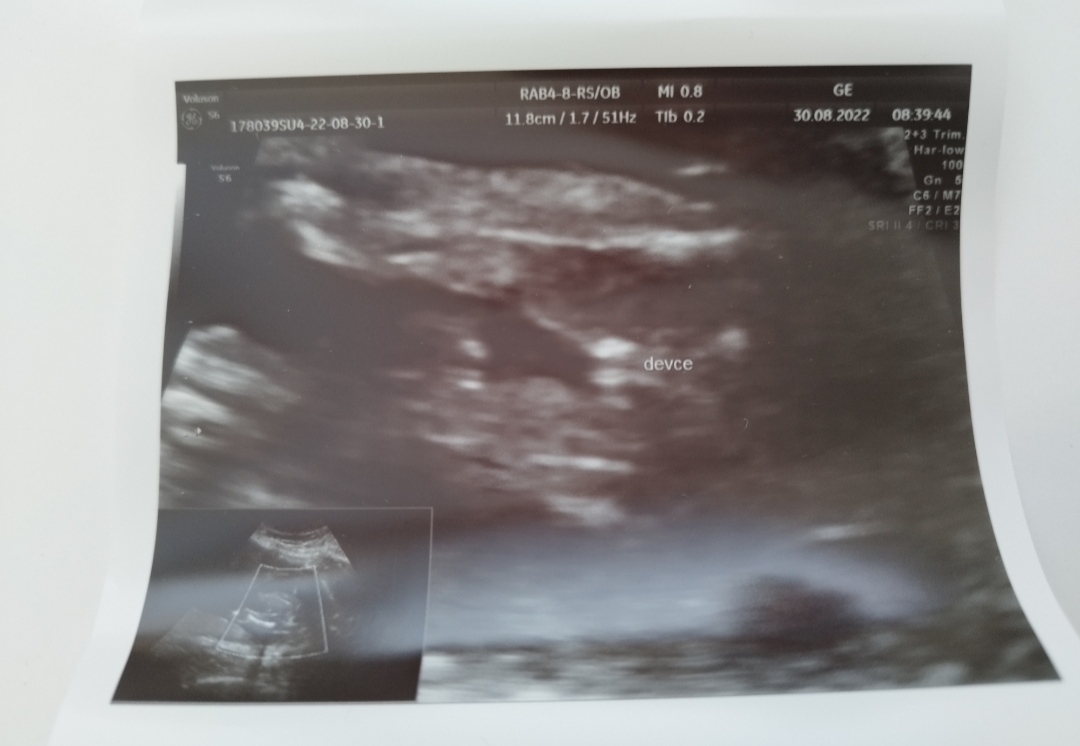

Hezký večer, je tohle pohlaví holčičky? Děkuji za vaše názory a odpovědi. Lékař mi to tam sice i napsal na fotografii ale nejsem si jistá.

To “kávové zrno”, ne? I když já prý taky čekám holčičku a co mi ukazoval dr bych fakt nepoznala nic 😂👌 a to říkal “tady je klitoris, tady stydké pysky 🫣🤷‍♀️“

Jak rika @inah91 je tam videt kavove zrno- stydke pysky.